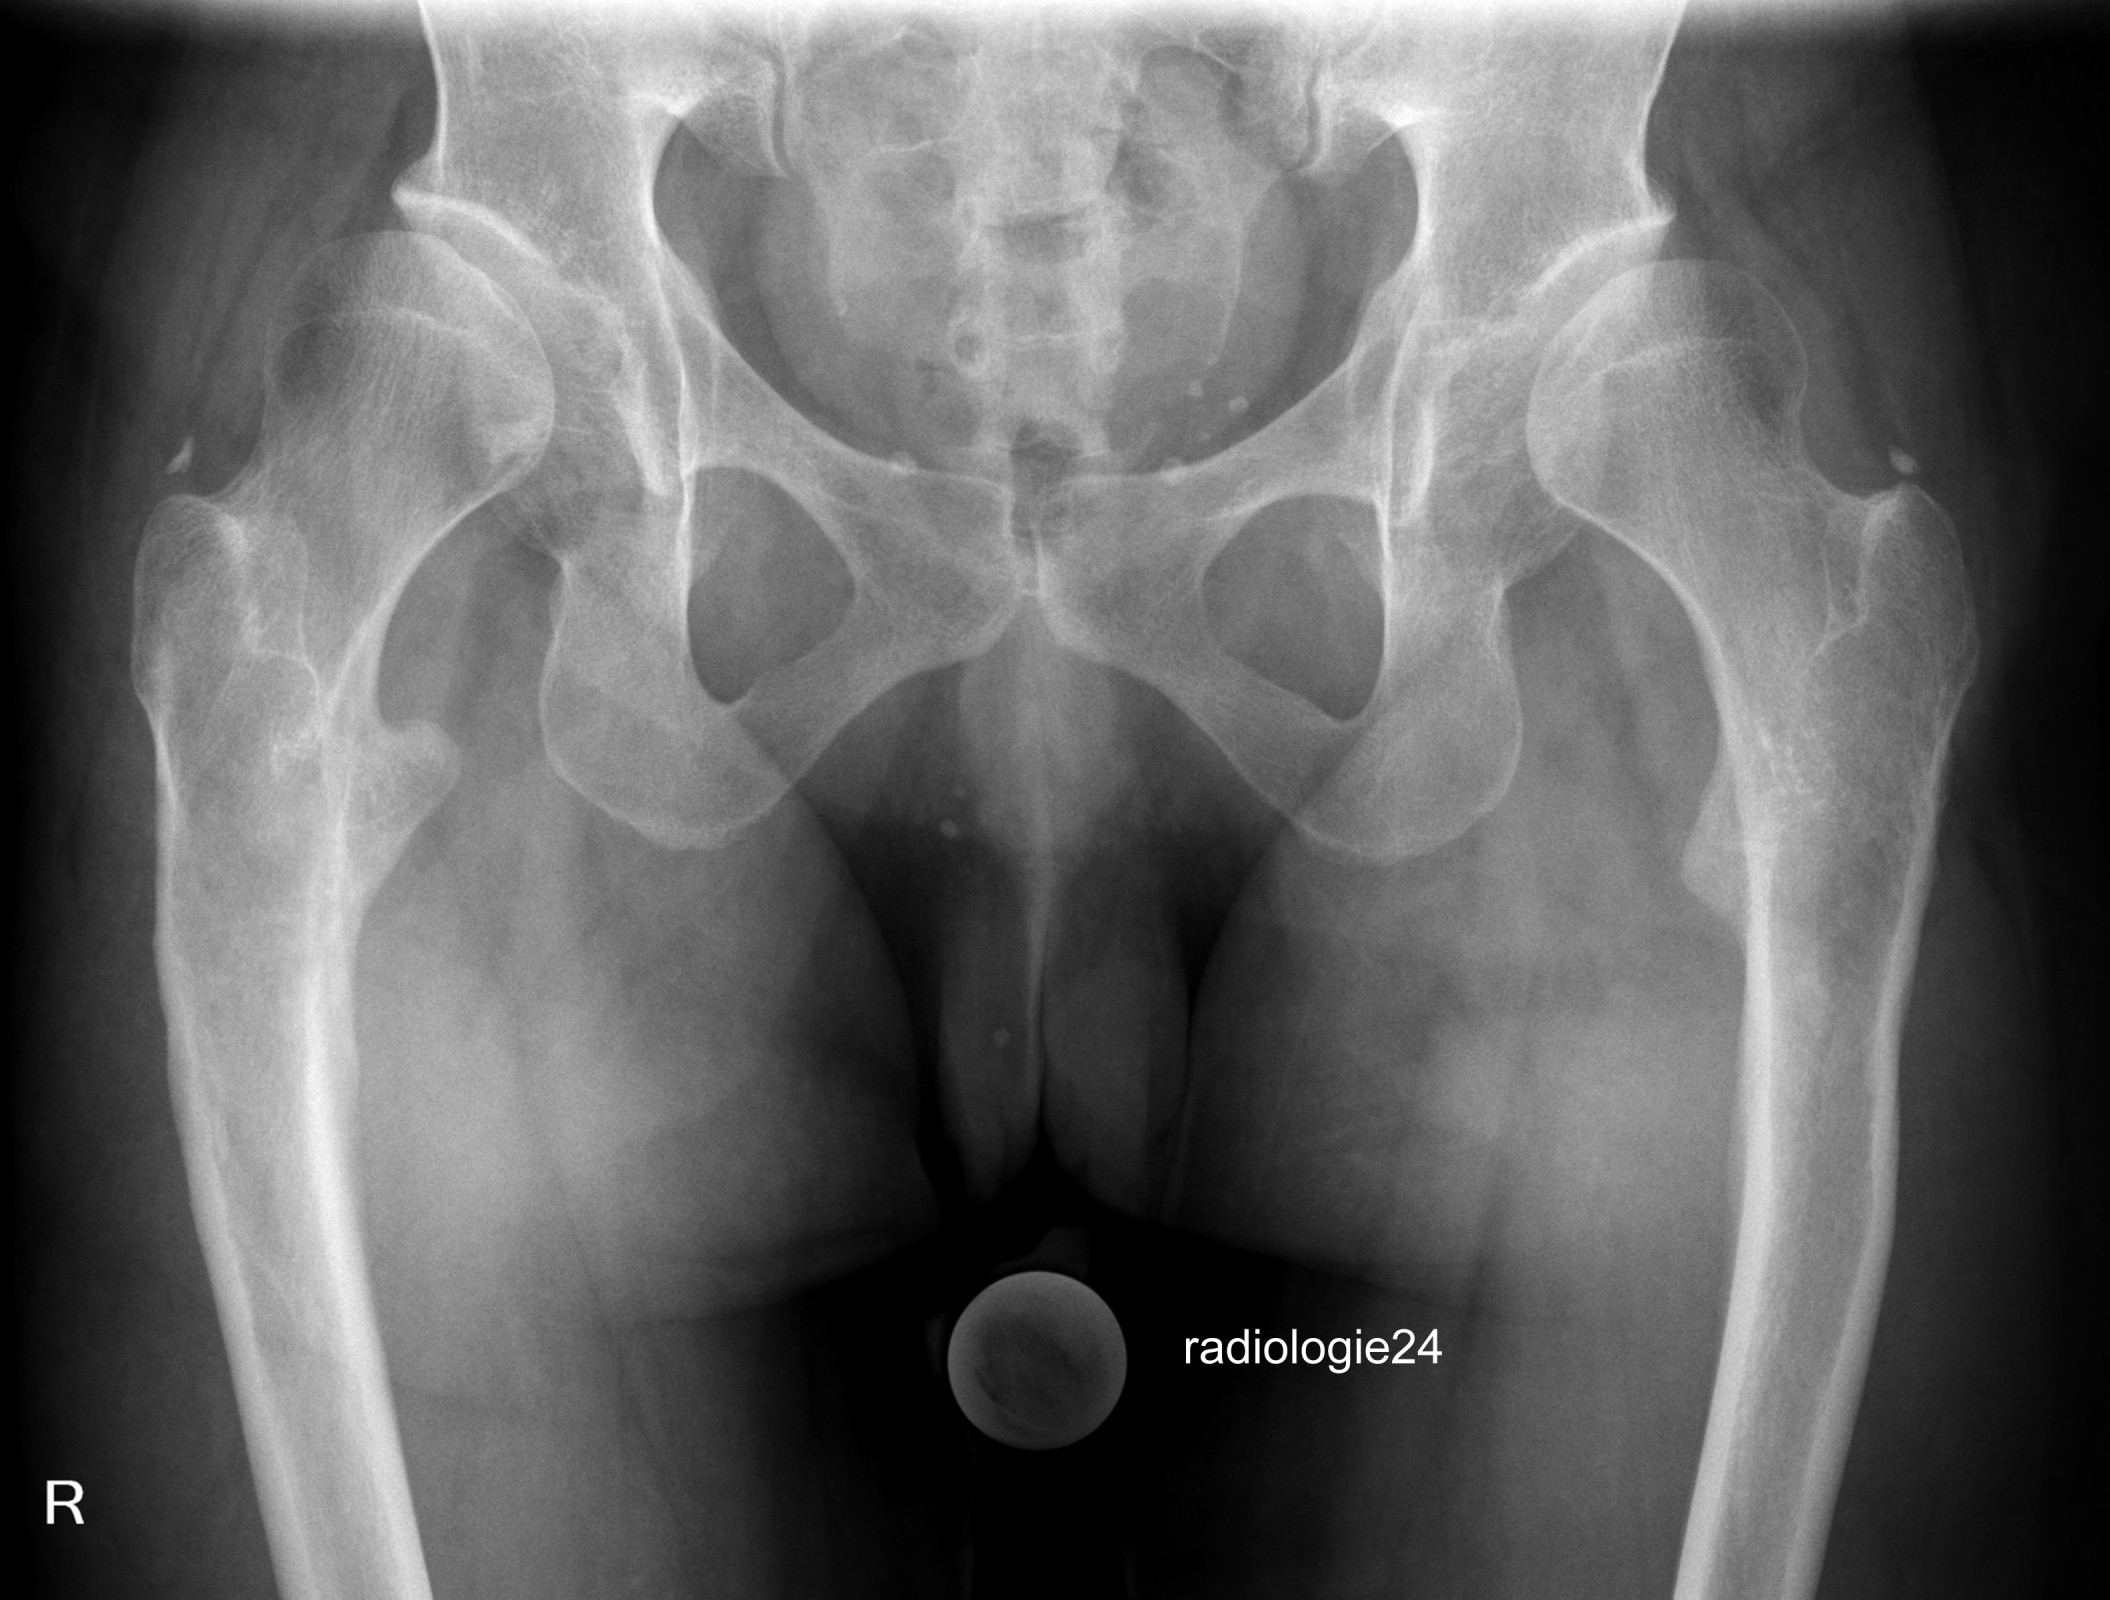

Röntgenfall des Monats Oktober 2018 mit Auflösung

34 jährige Patientin.

Progrediente Schmerzen in beiden Hüftgelenken. Z.n. Sturz.

Ihre Diagnose?

Weitere radiologische Diagnostik notwendig?